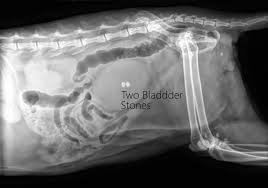

Crystals In Cat Urine And How To Treat Them Blue Buffalo

Crystals In Cat Urine And How To Treat Them Blue Buffalo from bluebuffalo.com

Stones, which are found in the bladder, are more commonly found in the lower urinary tract; Certain cat breeds, such as himalayans, have a genetic predisposition toward developing mineral deposits in the bladder. The compounds in the cat's diet will depend on the composition of the bladder stones. With a serious condition like bladder stones, in which the body needs the highest value nutrition possible for maintenance and repair of damaged tissue, we highly recommend a raw food diet for your dog or cat. How can u get rid of calcium stones? In some cats, struvite bladder stones form as a result of a urinary tract infection. They can remain small in size or grow to be several millimeters in diameter, and may rub against the bladder walls, causing inflammation. What are the clinical signs of oxalate bladder stones?

The stones may contain potassium, sodium, calcium or ammonia.